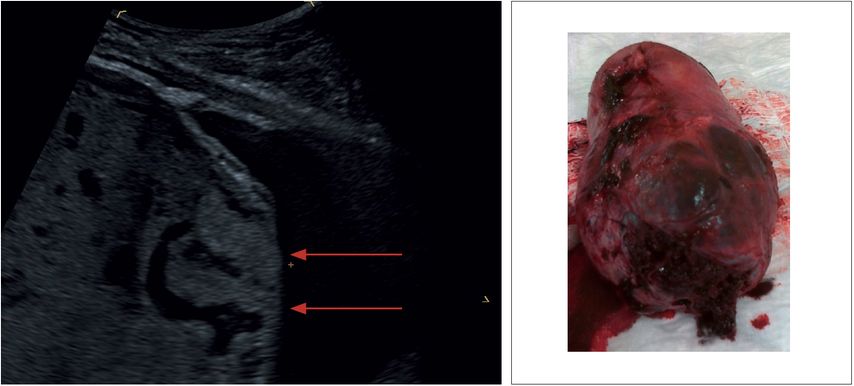

Im 2. Teil zum Einsatz der Methode der Dopplersonografie in der Pränatal- und Geburtsmedizin geht es um den klinischen Ein-satz. Die Erwartungen einer breiten Anwendung der Methode als Screeningverfahren haben sich nicht bestätigt. Allerdings spielen die Widerstandsindizes der Aa. uterinae im Rahmen eines multimodalen Ansatzes für die Vorhersage der Präeklamp-sie im 1. Was tun gegen Erhöhten Widerstand Aorta Uterina Hallo Hr Prof Dr Hackelöer, Ich bin in der 21 ssw mit meinem zweiten Kind schwanger . Der Gynäkologe hat in beiden Uterina Arterien erhöhte Widerstände festgestellt, ich habe morgen sowieso meinen Termin in der Pränataldiagnostik wo sich das mit Sicherheit genauer nochmal Sehr geehrter Herr Prof.Dr. Hackelör, in der 21.SSW ist bei mir ein linksseitiges Notching an der Gebärmuttervene festgestellt worden. Mir wurde gesagt, dass dieses noch bis zur 24. SSW weggehen kann. Was kann ich tun, um dies positiv zu beeinflussen und die Durchblutung zu fördern. In den letzten 3 Tagen bin ich außerdem sehr erschöpft und müde.

Sehr geehrter Herr Hackelöer, in der 24. SSW wurde bds. in der Arteria uterina ein erhöhter Widerstand festgestellt. Links: PI 1,33; RI 0,67 rechts: PI 1,50; RI 0,73 Nun wurde bei 26+0 nochmal kontrolliert und die Werte lagen bei links: PI 1,19; RI 0,63 rechts: PI 1,22; Rl 0,0,64 Beide Male war zum Glück kein Notching vorhanden Prädiktion Dopplersonographie A. uterina Ziel: Frühzeitige Risikoselektion Gegenwärtig einziger etablierter Parameter I. Trimesterscreening und bei 20 – 24 SSW Bilateraler Notch der Aa. uterinae Und/oder erhöhter Widerstand der Aa. uterinae Geringer Abfall des

Bleibt dieser Gefäßumbau aus, ist mit einer erhöhten Rate an Präeklampsien und Fällen fetaler Wachstumsretardierung zu rechnen, die ihrerseits im Dopplerspektrum mit einer postsystolischen Inzisur (Notching) oder mit erhöhten Widerstandsindizes einhergehen können ETS – erhöhter Widerstand A.uterina, Femur verkürzt Sehr geehrter Herr Prof. Hackelöer, ich habe heute die Ergebnisse von meinem ETS von 13+0 nach Vanishing Twin bekommen. In dem Arztbrief bin ich in die Hochrisikogruppe für Präeklampsie eingeordnet (1:31). Es wurde ein erhöhter Widerstand in der A. Uterina beidseits und Notching beidseits